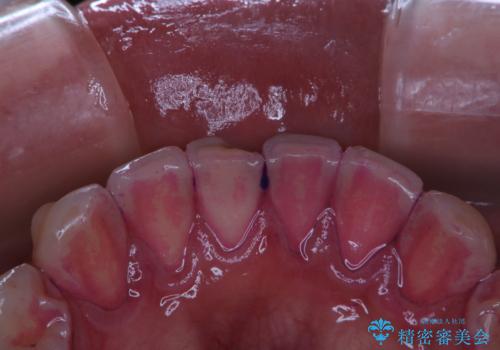

タバコによるヤニをPMTC(歯科医院での専門的クリーニング)で除去。